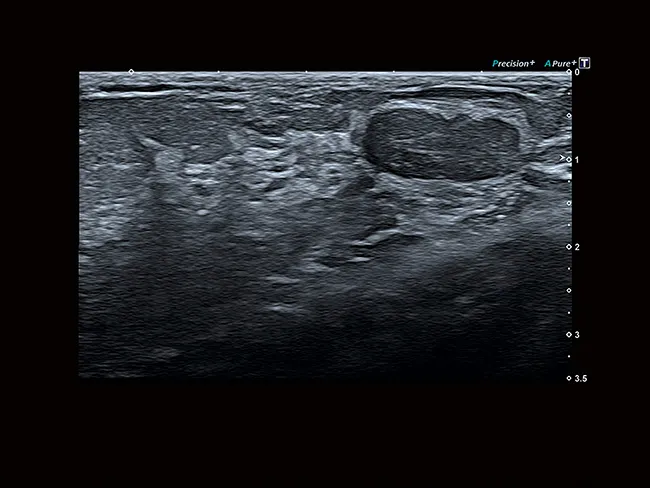

Уровень визуализации сосудов SMI в сочетании с высокой частотой кадров повышает достоверность диагностики при оценке поражений, кист и опухолей.